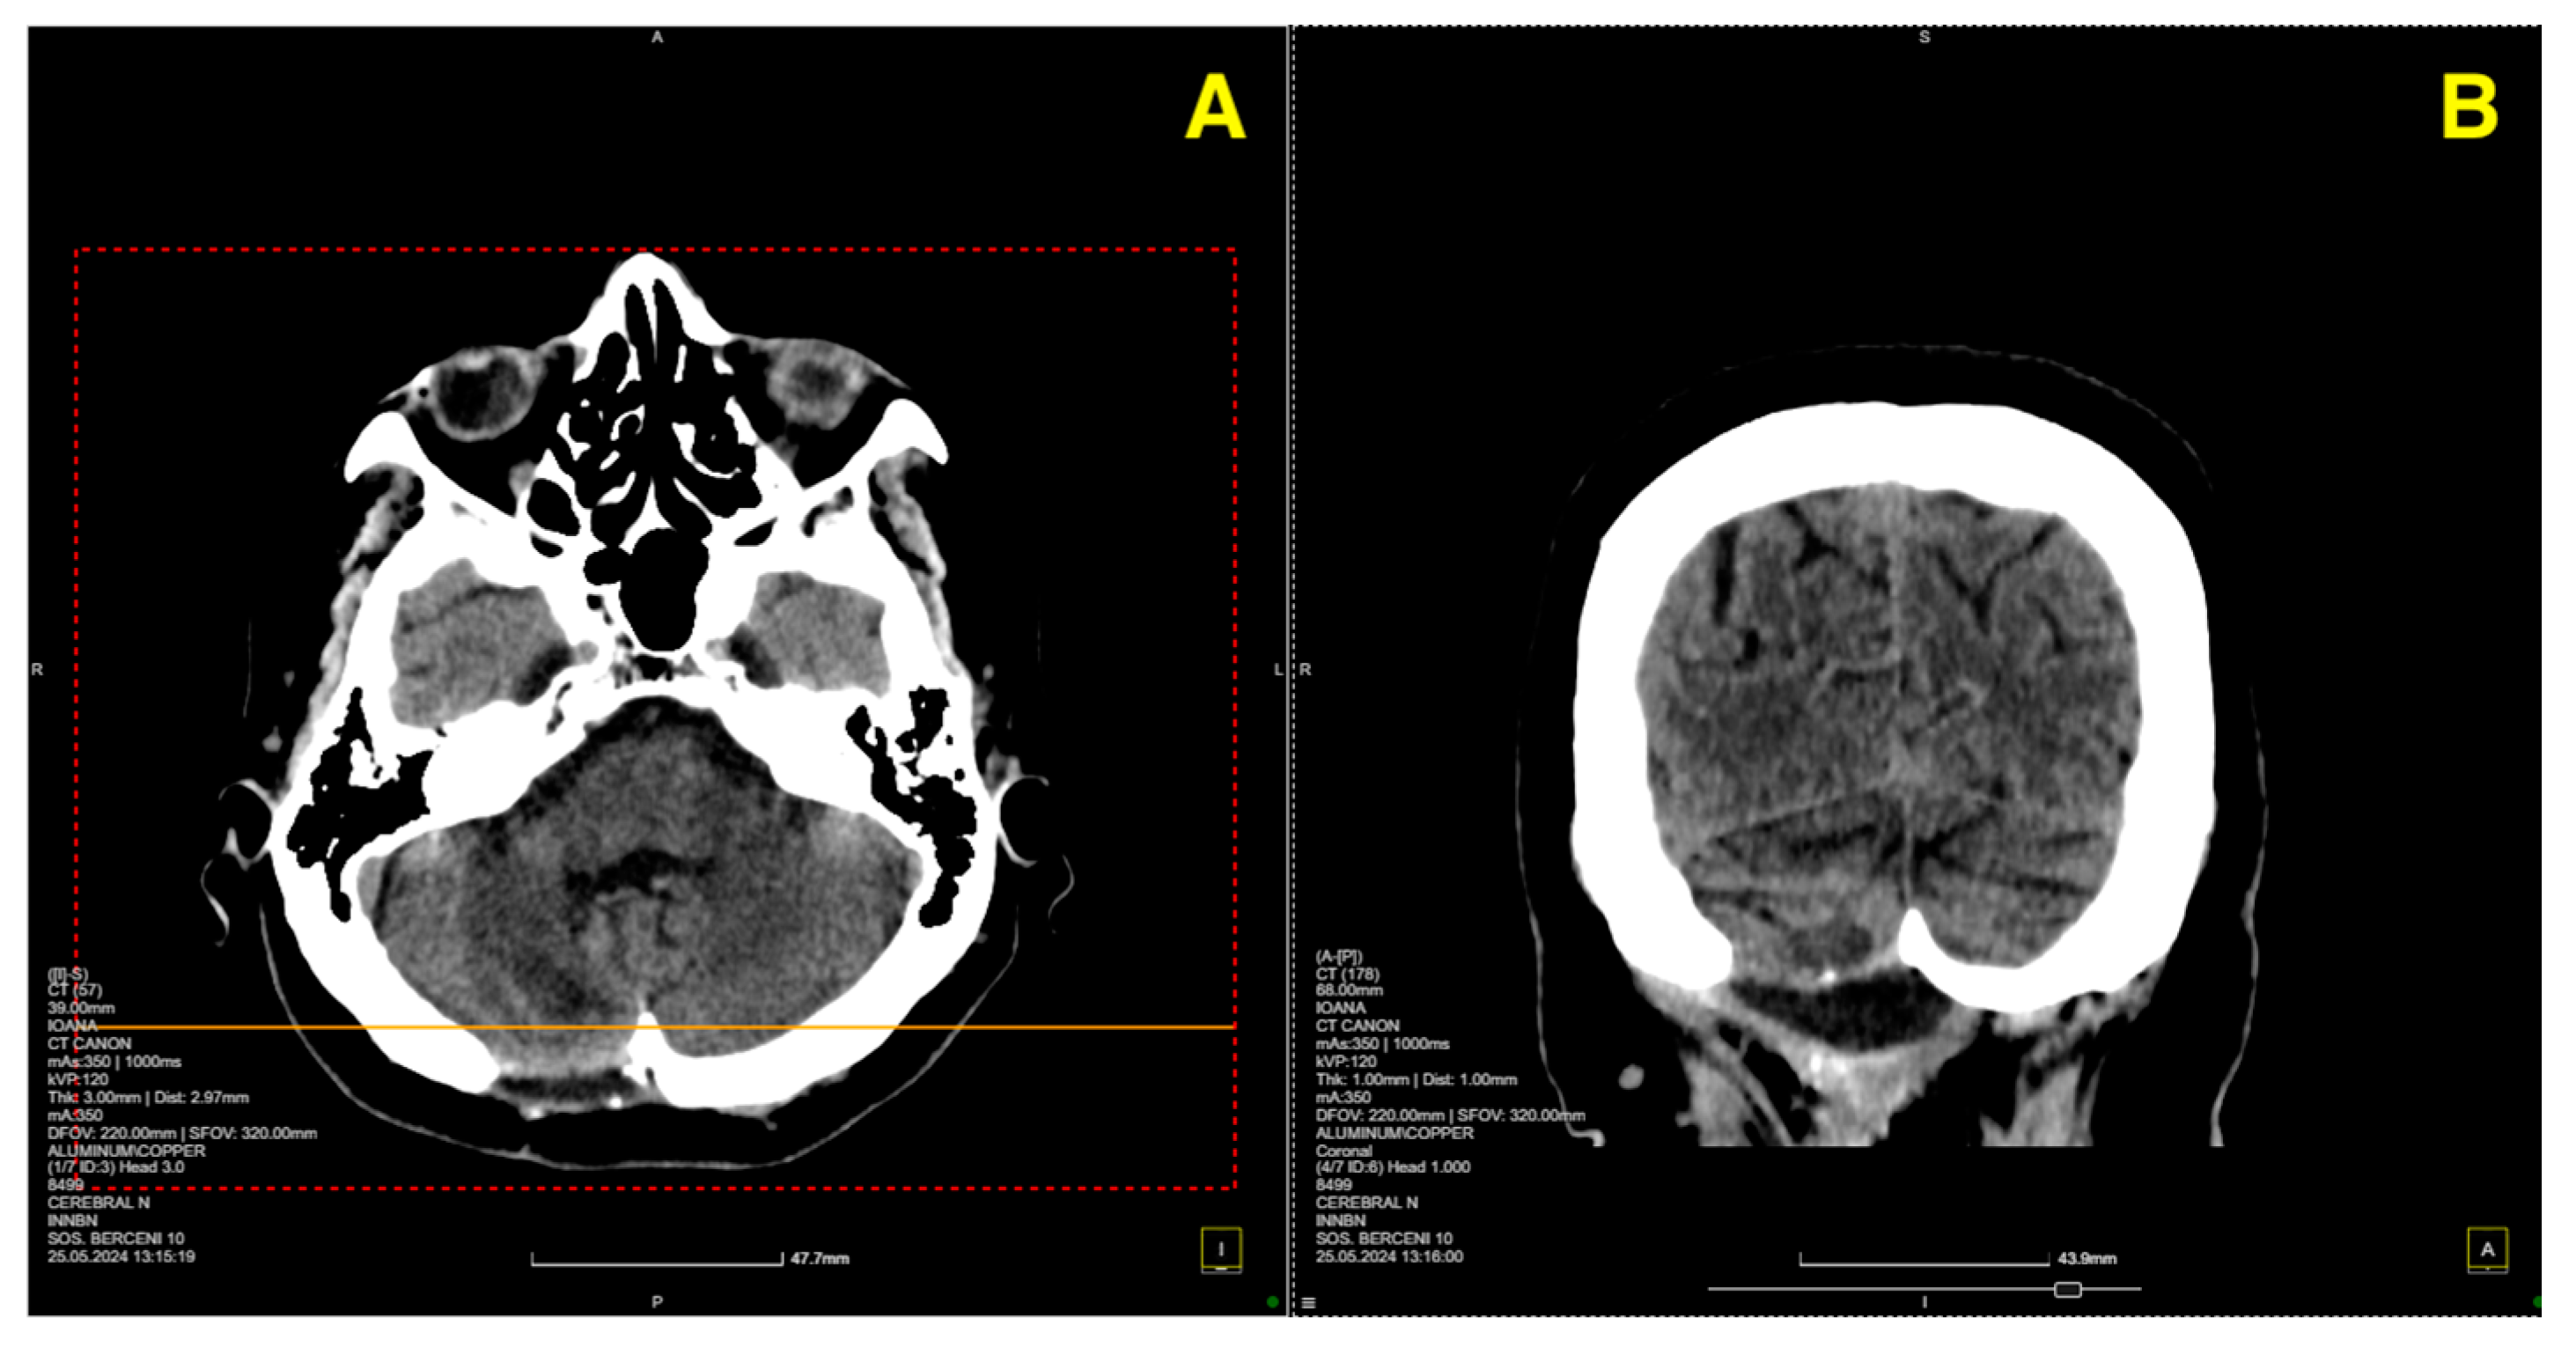

On postoperative day 5, a follow-up CT scan (Figure 3) was performed to assess the surgical site and confirm the absence of postoperative complications such as hemorrhage or hydrocephalus.

The two-month postoperative CT scan (Figure 4) confirmed excellent surgical outcomes. The right cerebellar hemisphere, where the cavernoma had been resected, demonstrated normal postoperative changes, with no signs of residual cavernous malformation or new lesions. The surgical cavity appeared stable, and no signs of hemorrhage or fluid collection were noted.

Figure 3. Five days post-op CT scan. (A) Demonstrated normal postoperative changes in the right paramedian posterior fossa. The site of the craniectomy was clearly visible, and no signs of residual cavernous malformation were observed. There was no evidence of acute hemorrhage, mass effect, or significant edema in the surrounding cerebellar tissue. Additionally, the ventricular system appeared normal, with no signs of hydrocephalus or midline shift. (B) provided further confirmation of the integrity of the bony structures and the absence of any complications related to the craniectomy. The surgical site remained stable, and there was no abnormal fluid collection or air entrapment within the resection cavity.

Figure 4. Two-month follow-up post-op CT scan. (A): Axial CT image of the right cerebellar hemisphere shows normal postoperative changes (red arrows) in the area of the cavernoma resection, with no residual cavernous malformation, new lesions, or signs of fluid collection or hemorrhage. (B): Coronal CT image further confirms the stability of the surgical cavity (red arrow), with no evidence of hemorrhage, recurrent lesions, or abnormal findings in the surrounding structures.